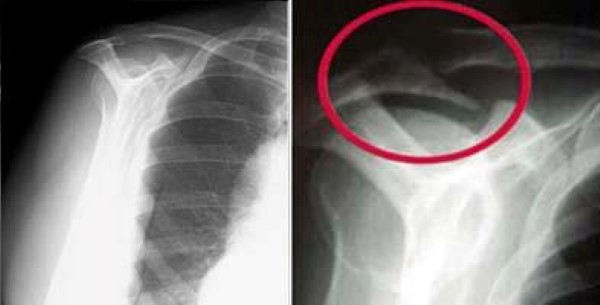

Get Shoulder Pain Bone Spur Images

Get Shoulder Pain Bone Spur Images. Bone spurs (also called osteophytes) are smooth, hard most bone spurs don't cause problems. But if they rub against other bones or press on nerves, you might experience pain and stiffness.

When needed, treatment may be directed at the causes, the. Bone spurs (also called osteophytes) are smooth, hard most bone spurs don't cause problems. They only require treatment when they start causing pain or discomfort.

Thousands of patients have had those bone spurs removed… and to this day many still do. When needed, treatment may be directed at the causes, the. Common symptoms of bone spurs include swelling, pain, and tearing in your muscles and tendons. Bone spurs do not require treatment unless they are causing pain or damaging other tissues.